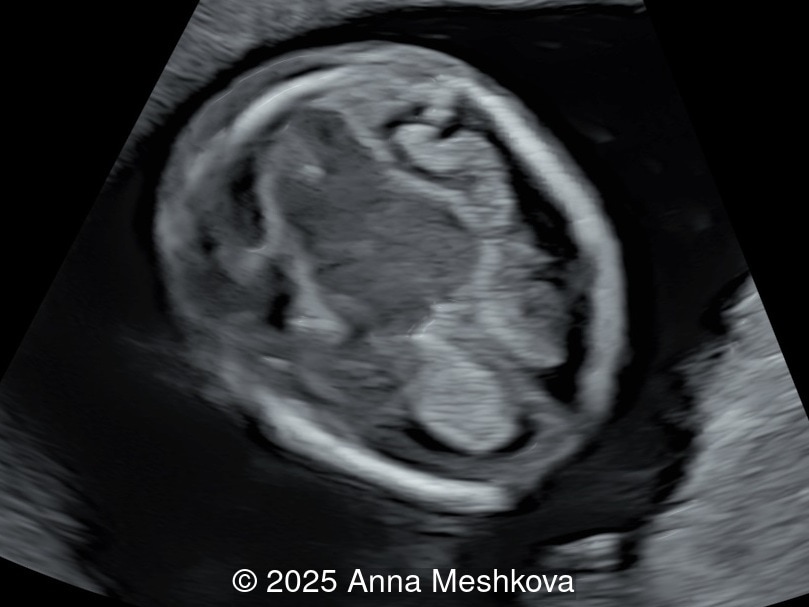

Image 2

• Image 2:  Transverse section of the brain at the level of the aqueduct of Sylvius. Midbrain is seen juxtaposed to the occiput, known as "crash" sign.

5.  The Crash Sign describes the posterior displacement and deformation of the mesencephalon against the occipital bone due to reduced intracranial pressure caused by cerebrospinal fluid leakage. This is a promising early marker seen in a majority of first-trimester open spina bifida cases.  During this posterior displacement, the mesencephalon meets the only firm cranial structure on its way, the occipital bone, and is compressed against it.  On mid-sagittal view the brainstem is thickened and shifted posteriorly [6].

In spina bifida, the midbrain is posteriorly displaced, eliminating the space between the cerebral peduncles and the occipital bone. The transition between the cerebral peduncles and thalami appears as two parallel lines instead of the normal acute angle

Image 12 In spina bifida, the midbrain is posteriorly displaced, eliminating the space between the cerebral peduncles and the occipital bone. The transition between the cerebral peduncles and thalami appears as two parallel lines instead of the normal acute angle